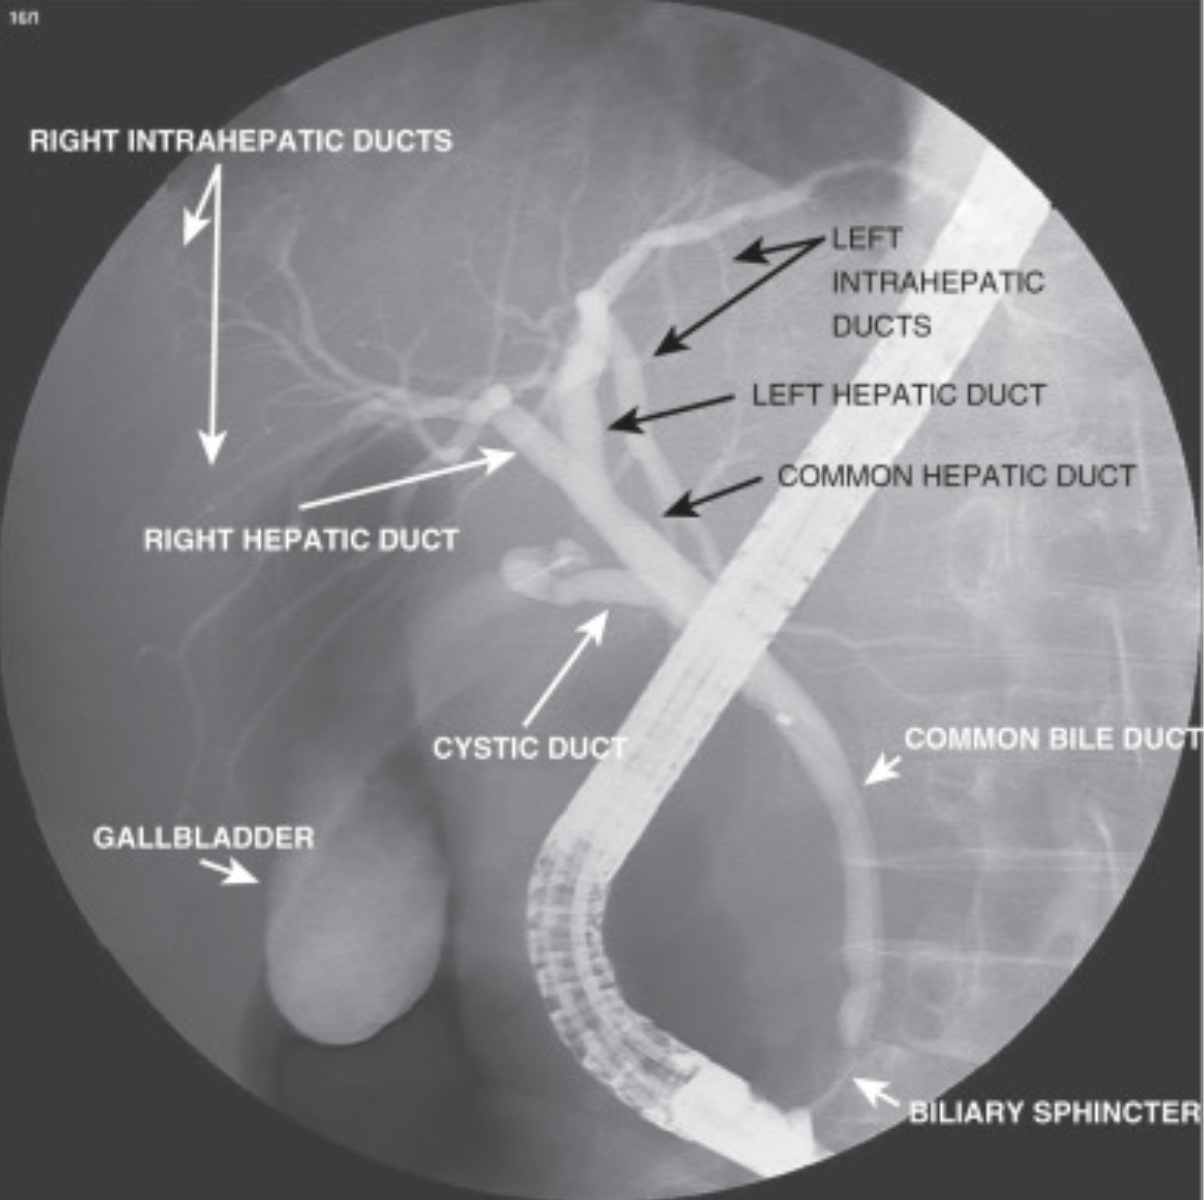

Endoscopic retrograde cholangiopancreatography, commonly known as ERCP, is a sophisticated medical procedure that combines endoscopy and fluoroscopy to diagnose and treat certain problems of the biliary or pancreatic ductal systems. This procedure is particularly useful for visualizing the ducts that drain the liver, gallbladder, and pancreas. Understanding what is an ERCP, its indications, procedure, risks, and benefits is crucial for patients and healthcare providers alike.

ERCP stands for Endoscopic Retrograde Cholangiopancreatography. It is a specialized technique that allows doctors to diagnose and treat conditions of the biliary or pancreatic ducts. The procedure involves the use of an endoscope, a flexible tube with a light and camera, which is passed through the mouth, down the esophagus, and into the duodenum. A catheter is then inserted through the endoscope into the bile and pancreatic ducts. Contrast dye is injected, and X-rays are taken to visualize these ducts.

4. Contrast Injection: Contrast dye is injected into the ducts, and X-rays are taken to visualize them.